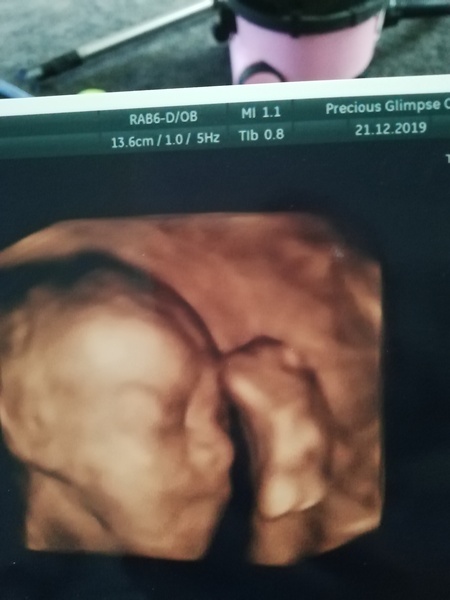

Jesskir89 · 22/12/2019 08:58

Hi ladies, how is everyone? Had my 4d scan yesterday, his legs are still up over his head but we got to see him sucking his bottom lip lol. Huge feet like his dad they're already 5. 6cm. I've attached a pic x

@Jesskir89 so cute!! Did you see a lot of details?

@whiskersonkittenss that was a rescan for me too as his legs were fully blocking his head last week where as this week he was just kicking himself with 1 foot haha. We didn't get to see as much as others due to his position but got a few looks and could see he has my dh nose :) @dinosauraddict good luck today please let me know how you get on, I'm there tomorrow x

@Jesskir89 aww what a cutie you've got 😍. We went for ours yesterday and she wasn't in a great position and kept puttin her hand up to her face so we've got a rescan on the 2nd Jan. we still got 3 or 4 nice pics though x

@Jesskir89 @DaniX91 beautiful scan photos, congrats!! I found the 4d video to be both amazing and also a bit frightening. Hard to believe there are no more scans now until the growth scan at 36 weeks :/. I guess they can't see much though after around this time.